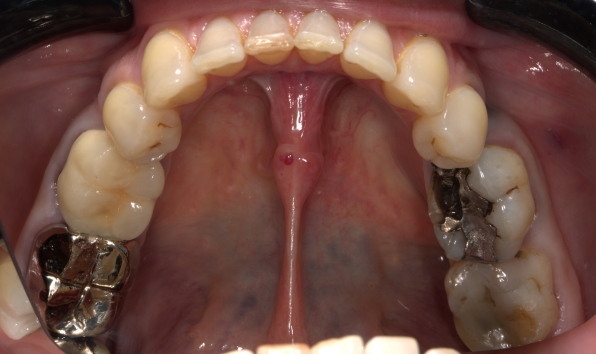

Onlay - case 1 before Before

Onlay - case 1 after After

Onlay - case 1